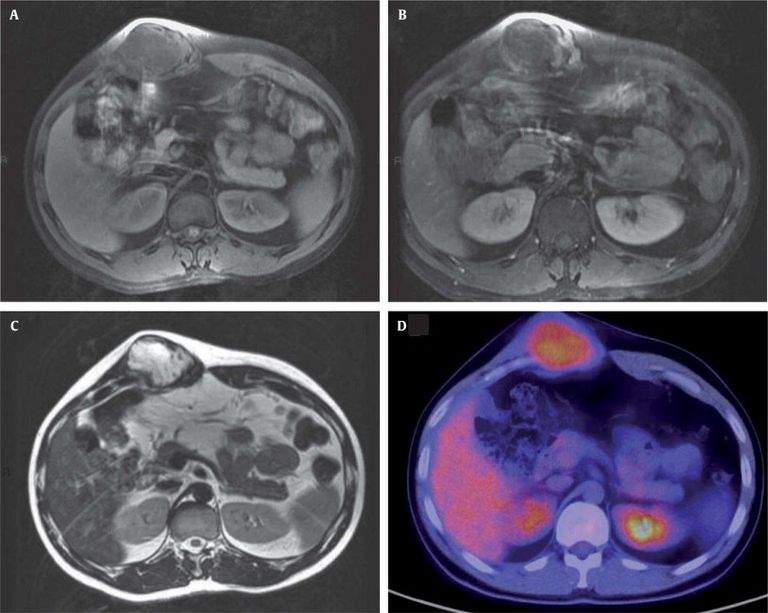

وعلق إيراني على حالة المريض الأول: "تعاملنا مع الشخص الأول بهذه التقنية في يوليو 2020، وبعد عام واحد يمكننا القول إن النتائج مذهلة، فالمريض هو رجل يبلغ من العمر 39 عاماً كان يعاني من آلام شديدة للغاية في منطقة نمو الورم، وهو الآن في حالة جيدة وقد اختفت الكتلة تقريباً، كل ذلك بفضل جلسة واحدة من العلاج بالتبريد".

أوضح الخبراء أن العلاج بالتبريد أو الاستئصال بالتبريد هو تقنية تجرى تحت إشراف الأشعة.

على وجه الخصوص، واحدة أو أكثر من الإبر التي يمكن أن تجمد مساحة حوالي 3 سم، يتم إدخالها داخل كتلة الورم والغاز الذي يتم حقنه يجمد الورم، ما يمنعه من الاستمرار في التغذية.

ونتيجة لذلك، فإن كتلة الورم نفسها تنكمش حتى تختفي.

ولذلك، فإن التقنية المستخدمة في معهد ريتسولي، جعلت من الممكن علاج أول 6 مرضى من جميع أنحاء إيطاليا، الذين تسير متابعاتهم بشكل جيد للغاية والتي سمحت أيضاً برؤية تحسن فوري في الأعراض، كما لاحظ الأطباء.